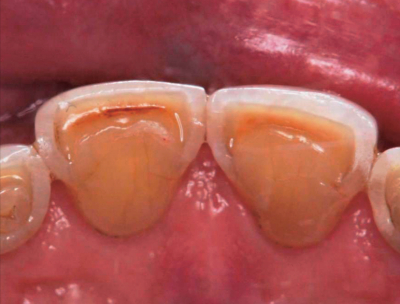

50歳の男性。上顎中切歯の舌感不良を主訴として来院した。5年前に気付いていたが、最近特に気になってきたという。初診時の口腔内写真を別に示す。

原因となり得るのはどれか。2つ選べ。

a. 破折

b. 齲蝕

c. 酸蝕

d. 咬耗

e. 着色